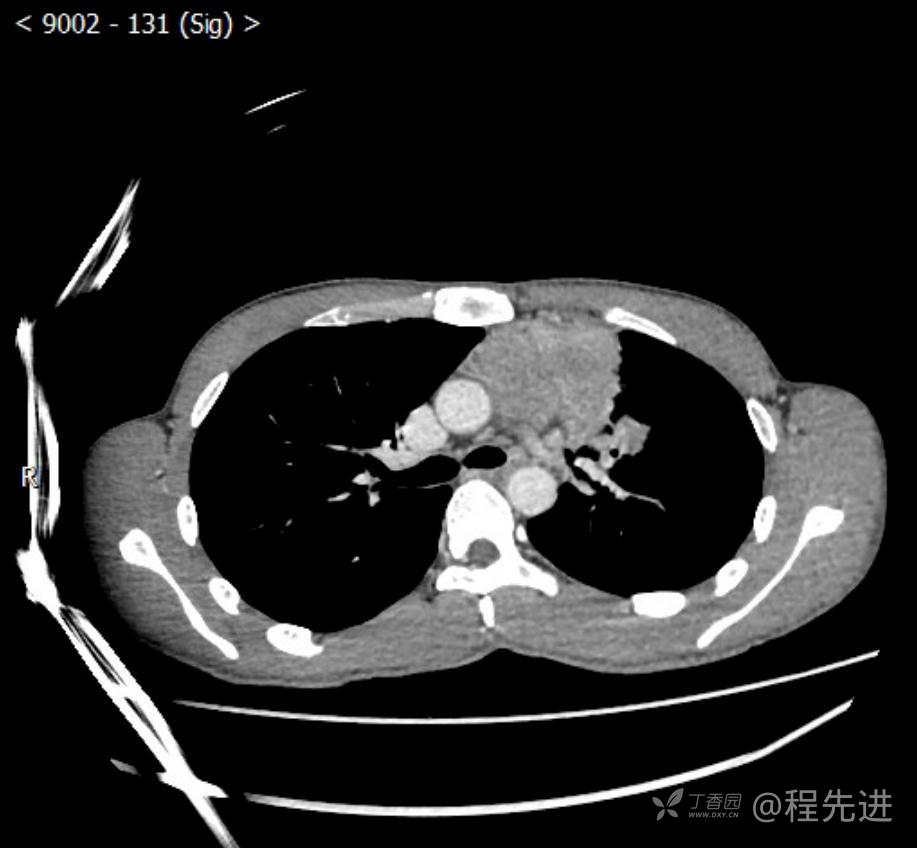

主诉:反复咳嗽1月,发现“纵隔”占位半月,乏力10余天。

现病史:患者1月前无明显诱因出现咳嗽,以夜间为著,伴有少量白痰,无发热,无胸痛、咯血,无痰中带血,未予重视,半月前外院行胸部CT检查发现“左前上纵隔”占位,未予进一步检查及治疗。近10余天自觉乏力,逐渐加重。